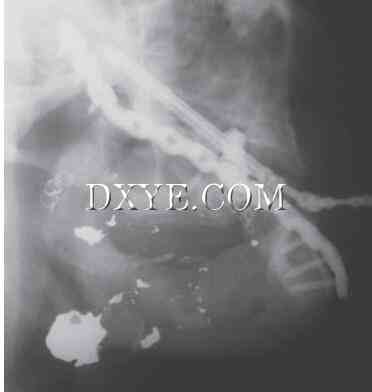

1.jpg

图29.1.  栓塞治疗出血。与火器伤下颌骨舌动脉栓塞病人的要求(注意线圈)防止失血过多。节段性缺损与牵引装置治疗。